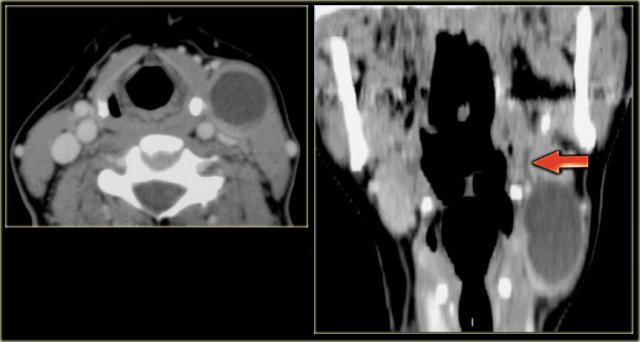

On the left images of a 21-year old female with a mass on the right.

This lesion is located between the internal and external carotid artery and therefore is a neural tumor.

The differential diagnosis is limited to tumors arising from the vagus nerve and sympathetic plexus.

On CT and color doppler the mass is clearly hypervascular and the only possible diagnosis is a paraganglioma.